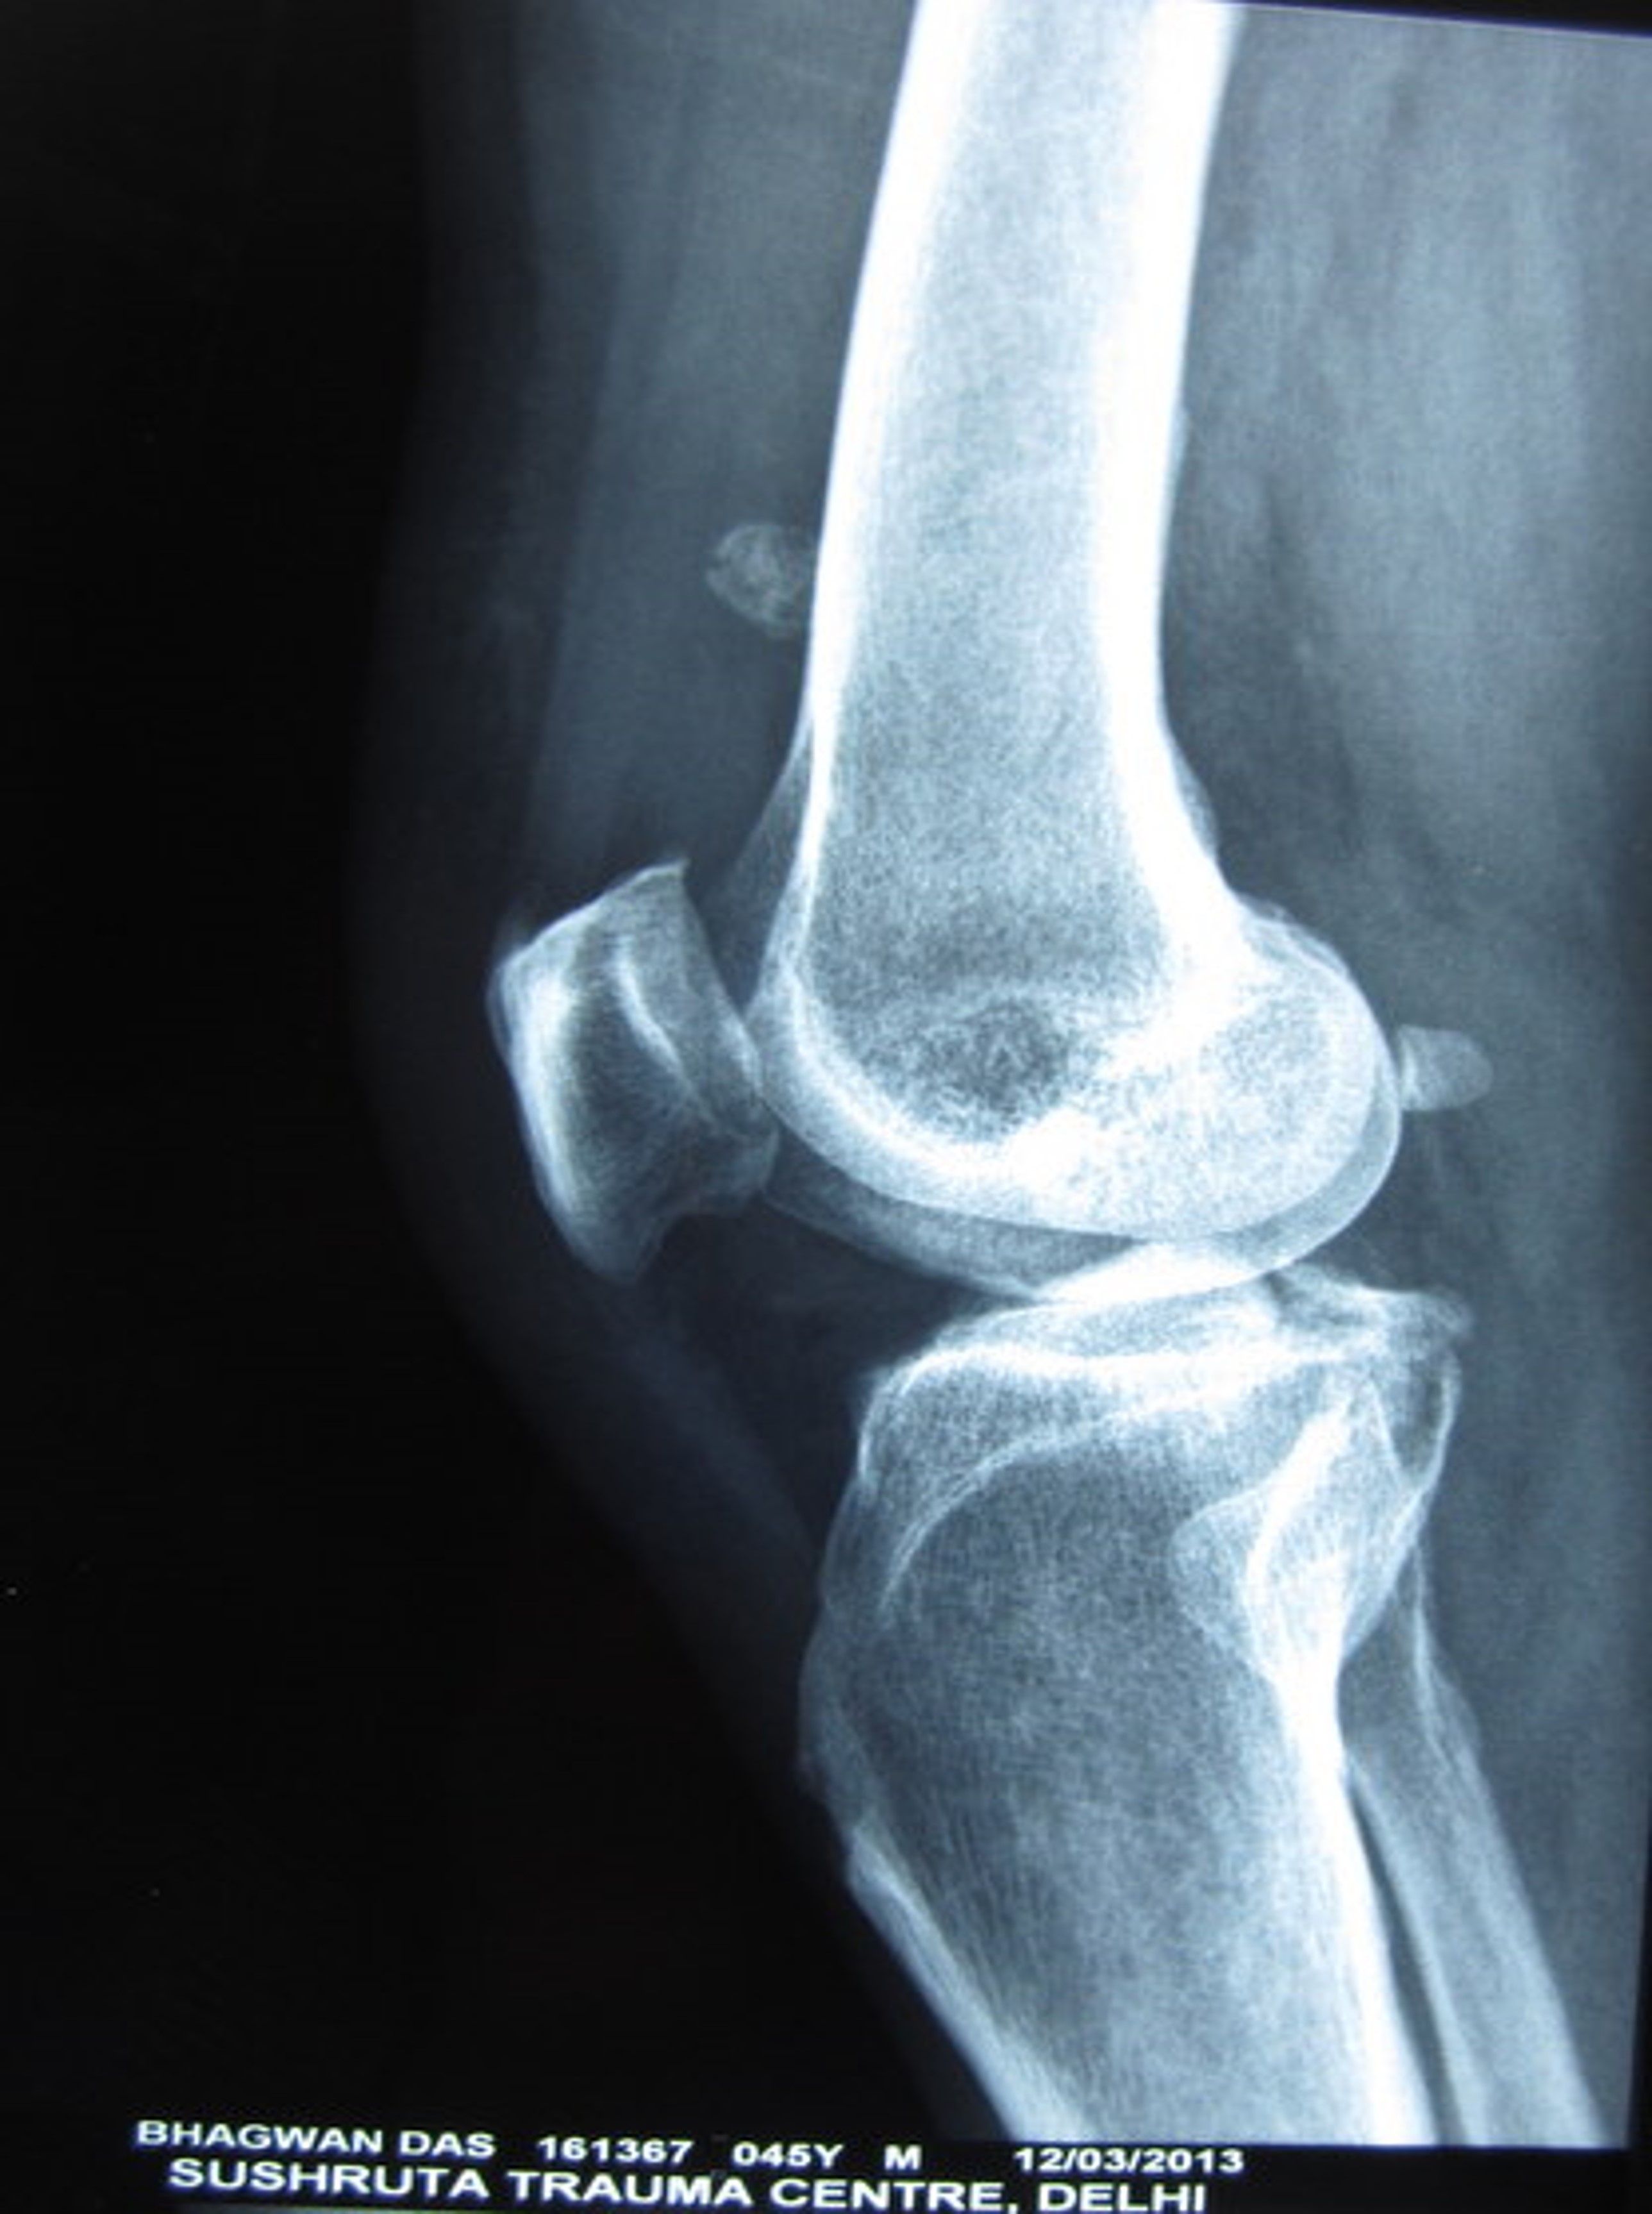

Case 1

Case 1 pre op xrays and post op xrays